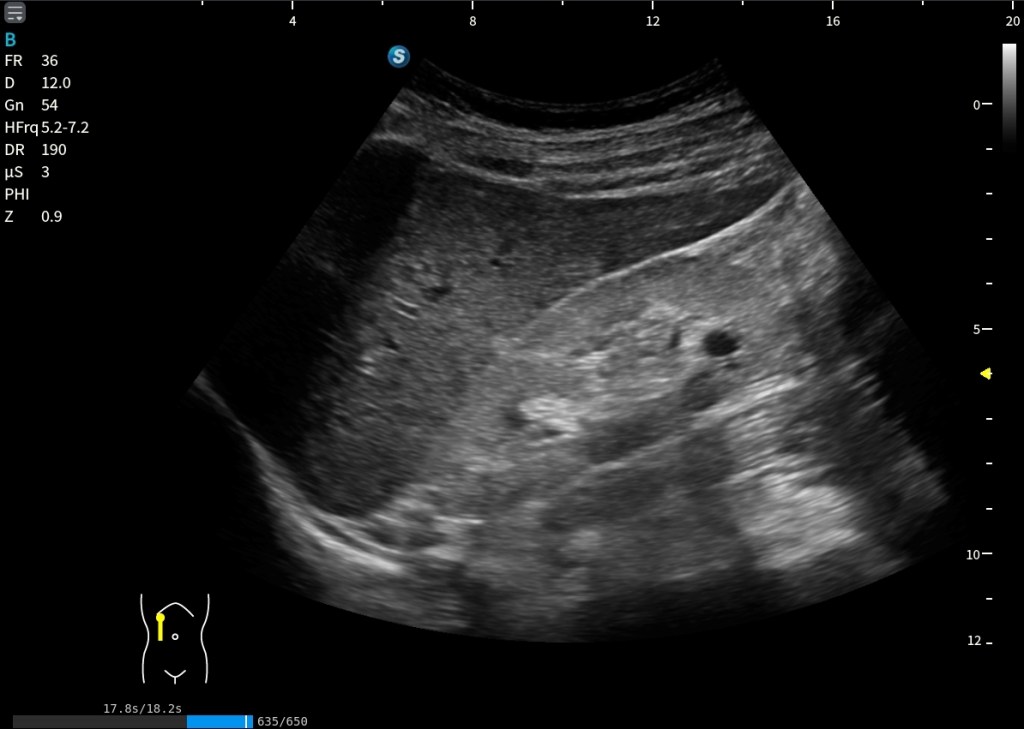

En la imagen siguiente, tenemos una inferior y una superior, en la superior estamos viendo una situación de normalidad. La corteza renal y el hígado se ven con la misma ecogenicidad. Es lo que buscamos siempre.

Sin embargo, en la imagen inferior la cosa cambia. Lo que observo es una hiperecogenicidad renal difusa del riñón derecho. El riñón se ve más brillante que el hígado de forma global, no es algo focal.

Está marcado con Normalidad y Patología.